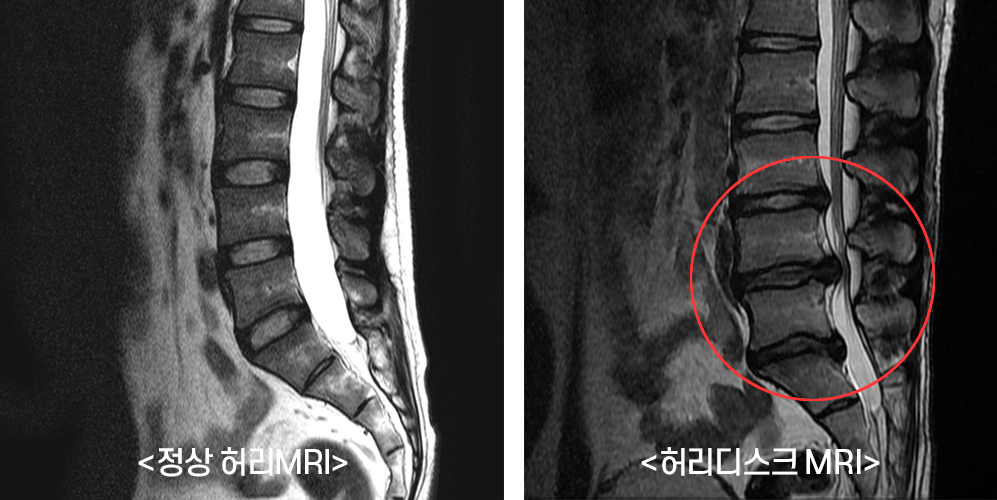

허리디스크의 이해

허리디스크는 척추의 구조를 이해하는 것이 중요합니다. 척추는 여러 개의 척추뼈로 이루어져 있으며, 이 사이에 디스크가 위치하고 있습니다. 디스크는 젤리같이 부풀어 있는 내부와 외부 섬유링으로 이루어져 있어 충격을 흡수하는 역할을 합니다. 그러나 여러 요인, 예를 들어 무리한 운동, 잘못된 자세, 노화 등으로 인해 디스크가 손상되거나 탈출하게 되면 심각한 통증을 유발할 수 있습니다.